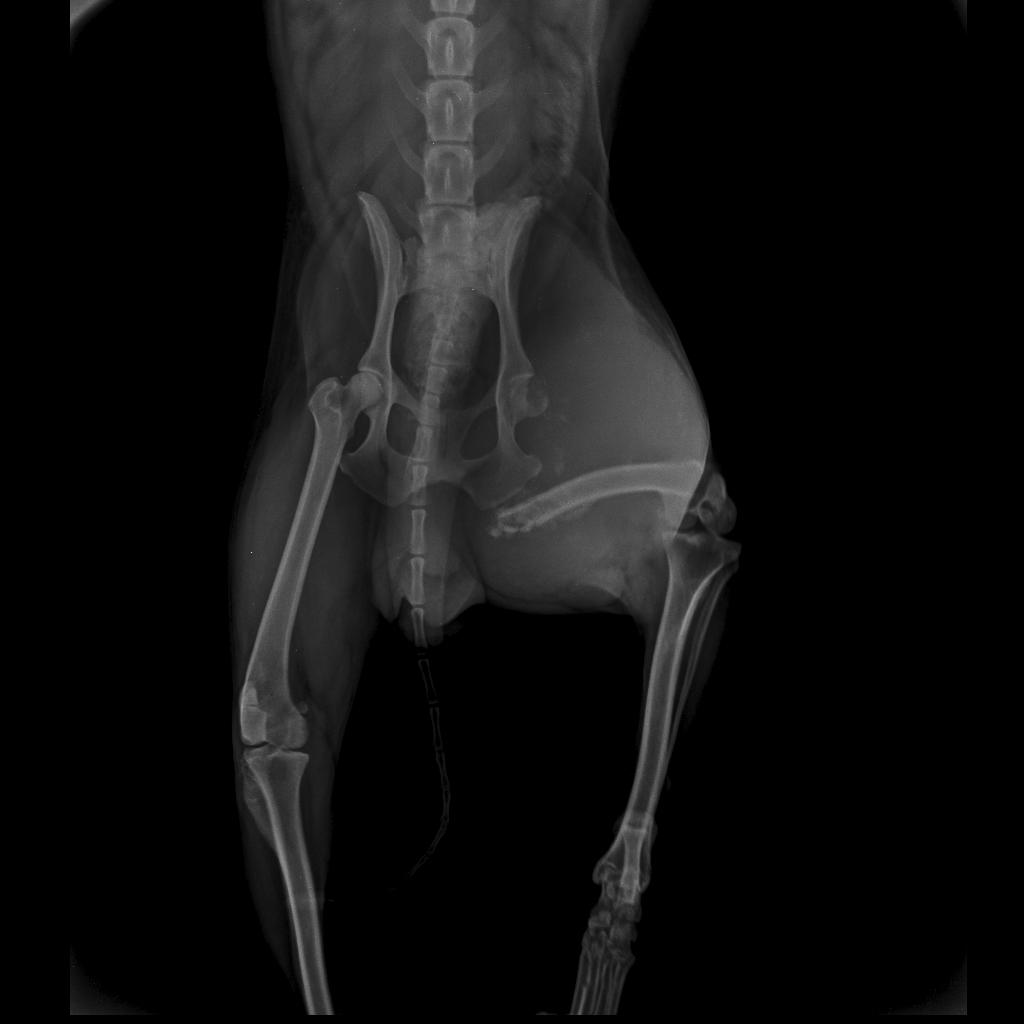

Bob é um cachorro de 9 anos, a uns 6 meses mais ou menos ele apareceu com a perna mancando e quando fez raio-x, o fêmur estava quebrada sem saber o motivo, pois desde pequeno ele nunca ficou em casa de ninguém, sempre fugiu para rua, Bob é muito querido onde mora mais não temos condições de arca com o que o veterinário pediu para cirurgia dele que custa 2,500 reais, qualquer valor será bem vindo.